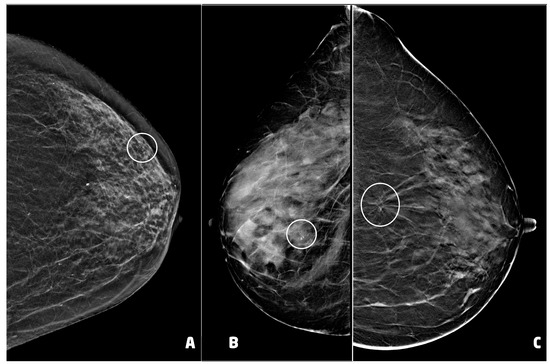

Post-procedural hematoma was found in 12 cases (14.1%) (Figure 5). According to the classification proposed by Schaefer et al. [24], two hematomas were classified as moderate while 10 as mild. Nine hematomas were found in women who underwent VABB with a 9 G needle, while the remaining three underwent VABB with a 12 G needle.

The post-procedural clip was correctly positioned in 75 of 85 procedures (88.2%). The clip was migrated cranially in four cases, caudally in four cases and externally to lesion in the remaining two cases. One woman showed both hematoma and migration of the clip after a procedure performed with a 9 G needle.

Figure 5. Post-procedural hematomas and clip placement (white arrows): (A) 55 year-old woman (see Figure 4C), clip in correct position with mild hematoma, two days after the procedure; (B) 62 year-old woman with lobular carcinoma in situ of the left breast, clip in correct position with moderate hematoma, two days after the procedure; (C) 66 year-old woman (see Figure 4A), clip in correct position with moderate hematoma.